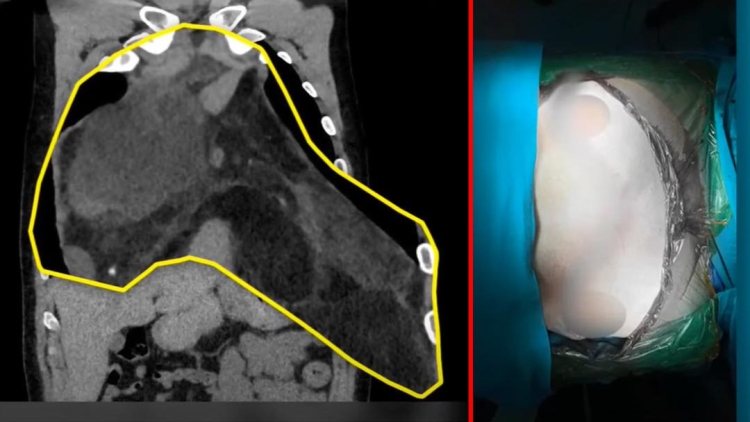

Aniden nefesi kesilen ve hastaneye başvuran Özgürel’in göğsünde 47 santimetre çapında ve 4 kilo ağırlığında dev bir tümör olduğu ortaya çıktı. Yapılan ameliyatla Türkiye’de kayıtlara geçen en büyük göğüs içi tümör başarıyla çıkarıldı.

“Göğüs kafesinin içini tamamen dolduran, sağ akciğerden başlayarak kalbi ezecek kadar baskı yapan ve sol akciğeri tamamen saran 47 santimlik bir kitleydi. Türkiye’de bilinen en büyük vaka. Dünyada da yalnızca 1-2 benzeri var.”

Tümörün büyüklüğü ve konumu nedeniyle klasik cerrahi yöntemler yetersiz kaldı. Prof. Dr. Demir ve ekibi, sternum kemiğini keserek göğüs kafesini tamamen açmak zorunda kaldı. Başarılı geçen ameliyat sonrası hasta sağlığına kavuştu.

“PET ve MR sonuçlarında hep 26 santimlik kitle dediler. Meğer 47 santimmiş. Şok geçirdim. İçimden bir yaratık çıkmış gibiydi.”